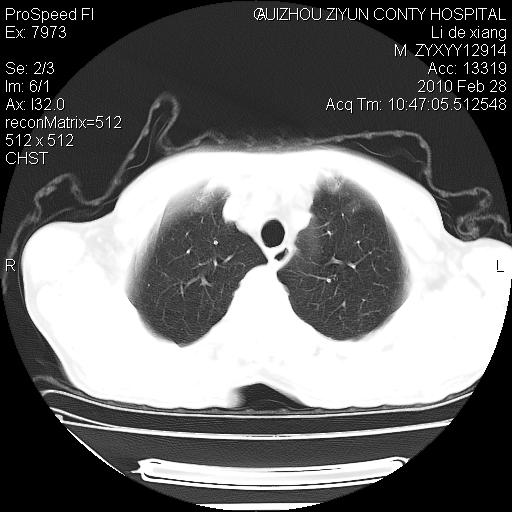

标题: CT24776:男 71Y 咳嗽咳痰胸痛两月,伴声音嘶哑。 [打印本页]

标题: CT24776:男 71Y 咳嗽咳痰胸痛两月,伴声音嘶哑。

左侧中央型肺癌伴左肺上叶阻塞性肺炎及节段性不张可能性大,建议纤支镜检查!

左肺门部肿块,伴左上肺斑块影,周边模糊,支持左肺中央型肺癌伴节段性不张及阻塞性肺炎,结合支气管镜检查。

左上叶支气管狭窄,阻塞性病变,肺门肿块,纵隔及肺门淋巴结增大,中央性肺癌

支持 左肺中央型肺癌伴左肺上叶阻塞性肺炎,纵隔淋巴结转移。